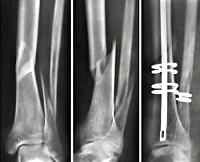

При оперативном лечении переломов большеберцовой кости используют различные металлоконструкции, в том числе – интрамедуллярные штифты, пластины и блокирующие стержни. Выбор способа остеосинтеза осуществляют с учетом характера и уровня перелома. В большинстве случаев предпочтительным является интрамедуллярный (внутрикостный) остеосинтез большеберцовой кости. Кроме того, при таких повреждениях широко используют внеочаговый остеосинтез аппаратами Илизарова – этот метод позволяет восстанавливать нормальное взаиморасположение отломков не только одномоментно (во время операции), но и в послеоперационном периоде. Он может применяться для лечения самых сложных повреждений, в том числе – раздробленных переломов с образованием дефекта кости. Недостатком методики является наличие массивной и неудобной внешней металлоконструкции.